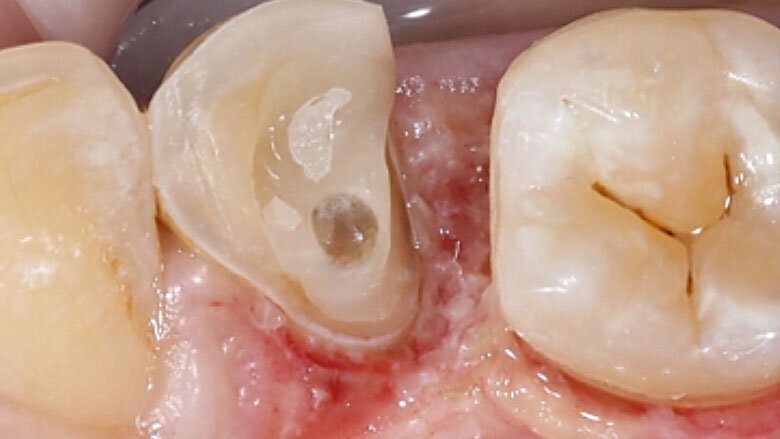

Fig. 1. Situación inicial: el diente 34 estaba fuertemente dañado. La encía se había adentrado en la cavidad.

Una paciente de 48 años acudió a la clínica porque el diente 34 se le había fracturado y otro odontólogo le había sido previamente que no se podía salvar. Durante el examen clínico se observó un defecto distooral muy extendido. La encía se había adentrado en la cavidad. La radiografía reveló una obturación insuficiente del canal radicular. Dado que una preparación de corona completa habría provocado una pérdida de las zonas de pared vestibulares y mesiales del diente, se decidió realizar una endocorona con VITABLOCS Mark II. Tras la gingivectomía, se reconstruyó el diente 34 con composite mediante láser y se llevó a cabo un tratamiento de revisión.